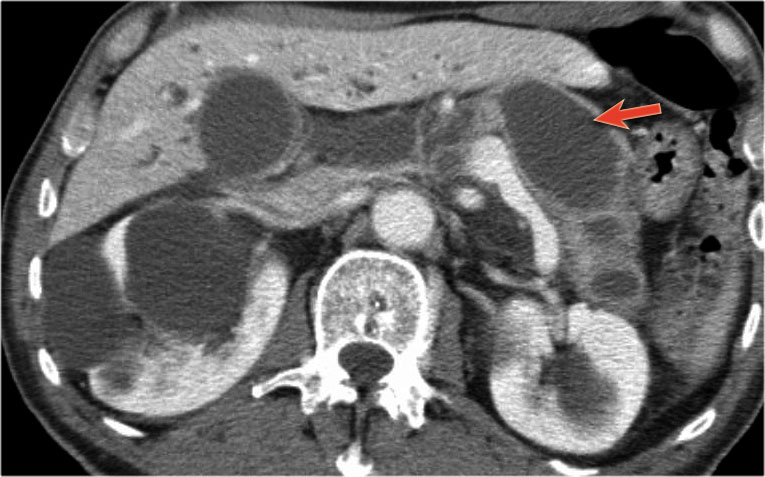

Bệnh nhân này bị viêm tụy mạn tính.

Lưu ý các vôi hóa ở đầu tụy (mũi tên cong).

Có nhiều nang giả tụy lan dài vào tận trung thất, gây chèn ép tim (mũi tên đỏ).